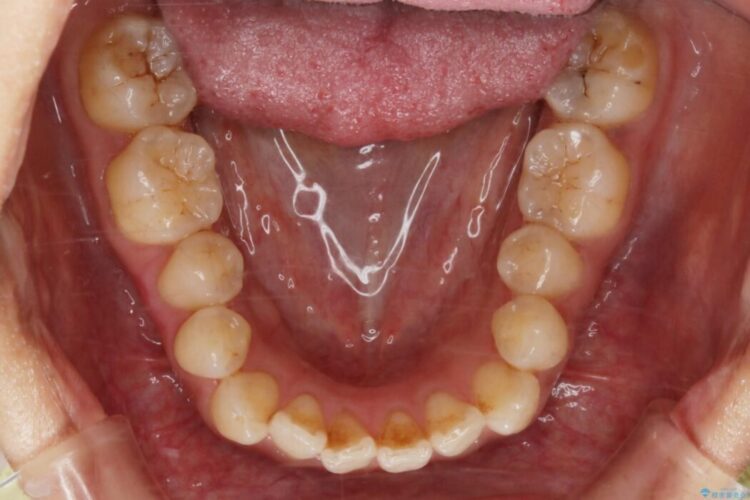

開咬により上下の噛み合わせが悪く、歯列の凸凹も合わせて治療したいとのことで来院されました。

なるべく非抜歯にて治療をするためインビザライン(マウスピース)とマイクロインプラントを併用した治療を行いました。